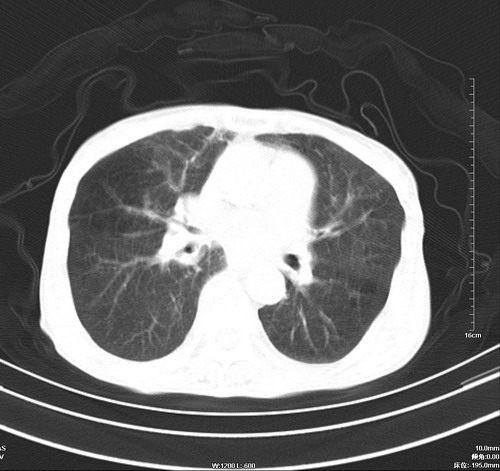

病人,女,79岁,主要因腹疼二月入院,彩超,肝,胆,脾,未见异常,胸透上消化道造影未见异常,化验白细胞增高,内科医生让做胸部ct检查,因为熟人多做了腹部(外科会诊考虑胆囊炎).现ct片如下请假各位战友.

1 气管旁、隆突下淋巴结明显肿大,肝左叶外侧段低密影,都考虑转移。

后中纵隔团块影,伴气管、食道受压移位,首先考虑转移瘤,肝s5段低密度灶。建议增强检查,另外其结肠是否有问题请提供,右肺部分肺叶局限含气增多,考虑局限肺气肿。

建议强化检查,考虑纵隔型肺癌,小细胞可能性大。

后中纵隔淋巴结肿大,首先考虑转移瘤。